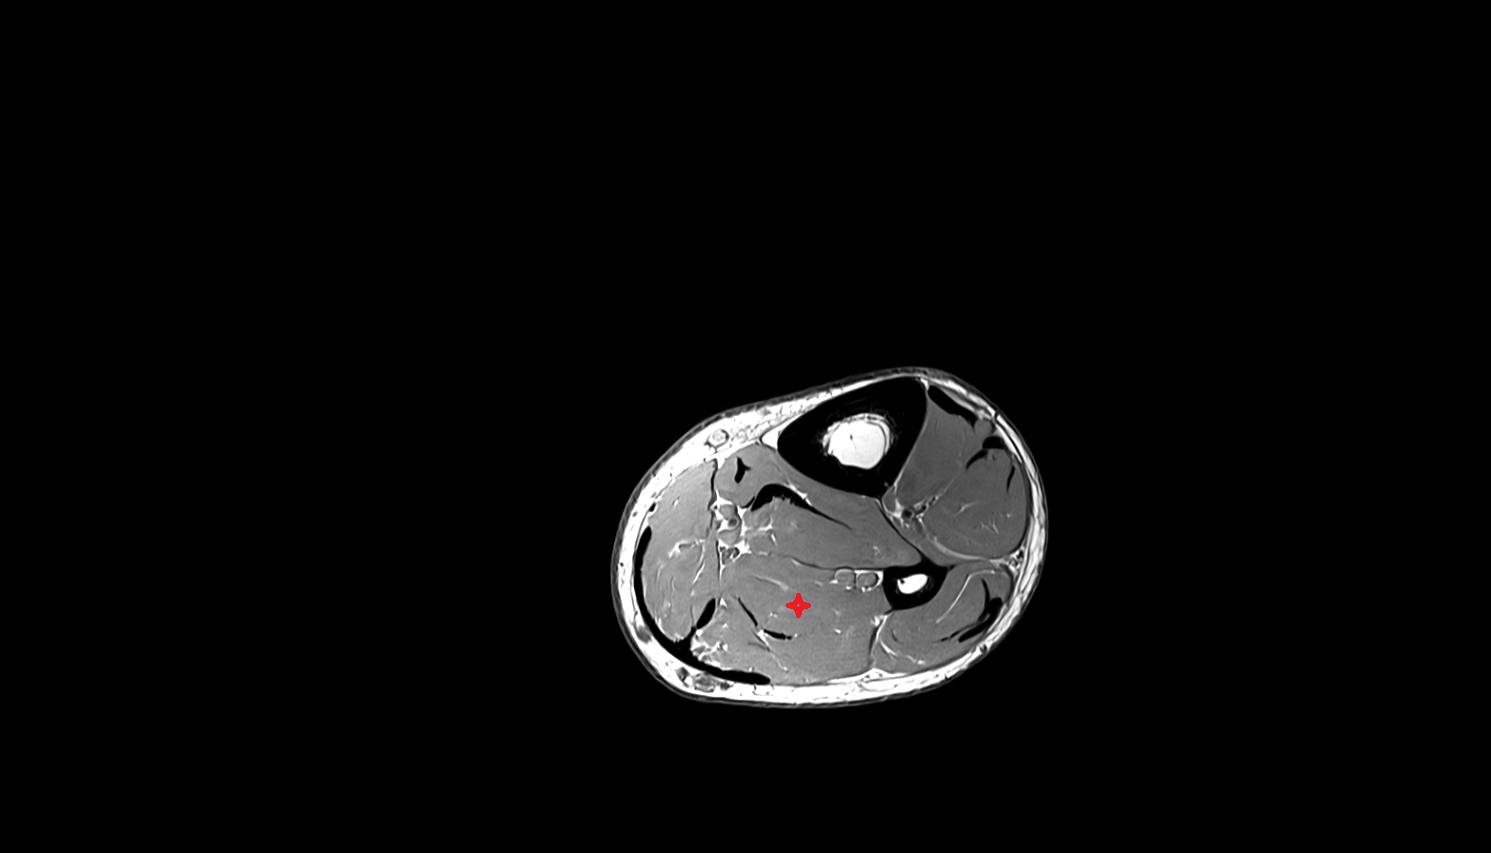

- Lateral head of gastrocnemius muscle

- Medial head of gastrocnemius muscle

- Gastrocnemius muscle

- Popliteus muscle

- Soleus muscle